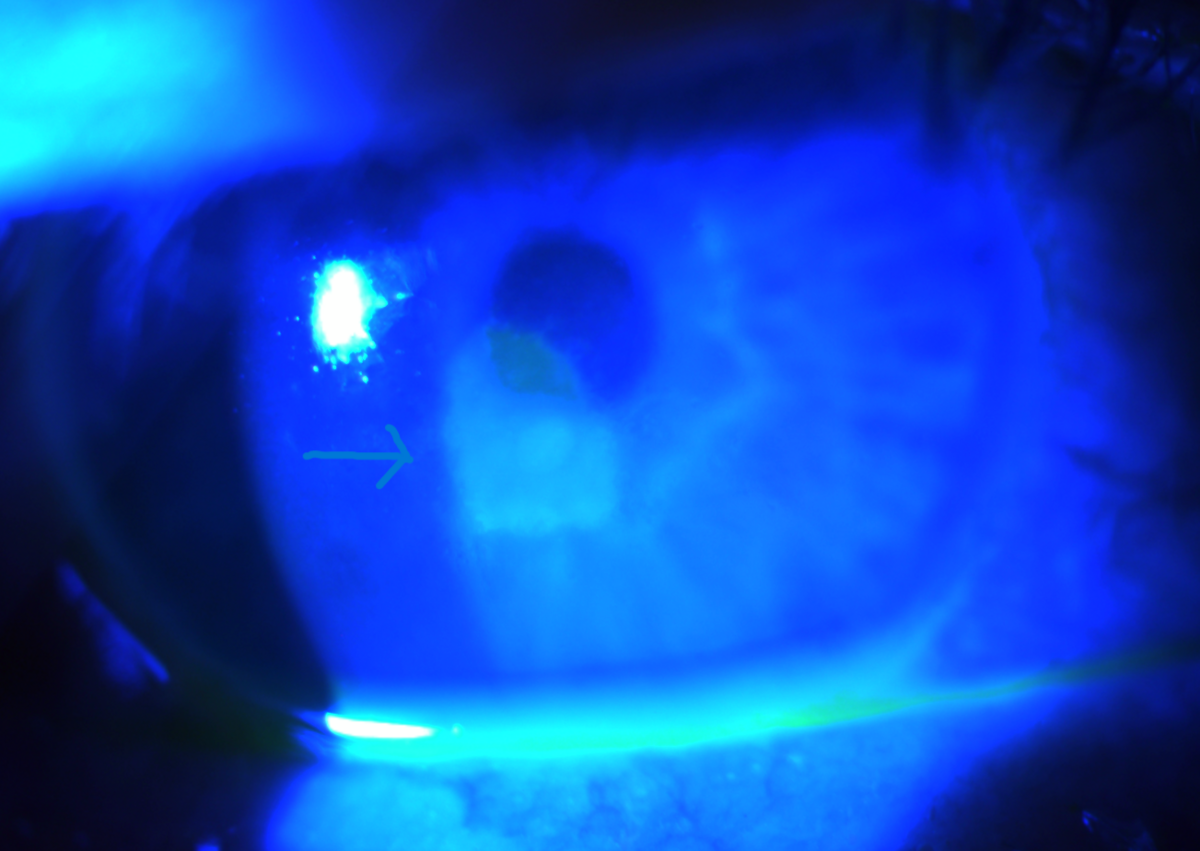

However, there are two surgical options that are available to many: LASIK (short for Laser-Assisted In Situ Keratomileusis), and PRK (short for Photorefractive Keratectomy). Both methods are forms of laser eye surgery, and both have comparable success rates and effectiveness for correcting vision. They both “add in” an additional, corrective lens before the light ever reaches your eye’s lens, by shaping a new one in your eye’s corneas.

The major difference in procedure is that, with LASIK, they cut a flap into your cornea and “carve” a new, corrective lens into your cornea’s interior, then fold the flap back over and let it heal. With PRK, there is no cutting, and instead they remove the top layer of your cornea and etch a new lens onto the underlying layer, then allowing the outer layer of your cornea to grow back and heal. These procedures differ in terms of pain/discomfort (PRK can be quite painful, LASIK is painless) and in terms of recovery time (LASIK is very fast, PRK is much slower).

It might seem like LASIK would be the option that everyone would choose, but whether you’re a good candidate for LASIK or not depends on your anatomy in a way that PRK doesn’t. Human corneas are relatively thin parts of your eye: typically only about half-a-millimeter thick, and subdivided into several layers. There’s a risk, if you attempt to cut a flap into someone’s cornea and their cornea is too thin, that instead of successfully making a flap that then gets folded back to enable the engraving of a lens, the top layer of the cornea can be accidentally removed entirely.

This is why the thickness of your cornea is one key to determining whether you’re a good LASIK candidate: if your cornea is ~500 microns thick or more, you’re likely an excellent candidate as far as corneal thickness goes. If your cornea is slightly thinner, you may still be a good candidate, but if your cornea is severely thinner (say, ~480 microns or less), most doctors will instead recommend PRK, or a variant of PRK known as ASA: Advanced Surface Ablation, which is sometimes called “flapless LASIK” for marketing purposes.